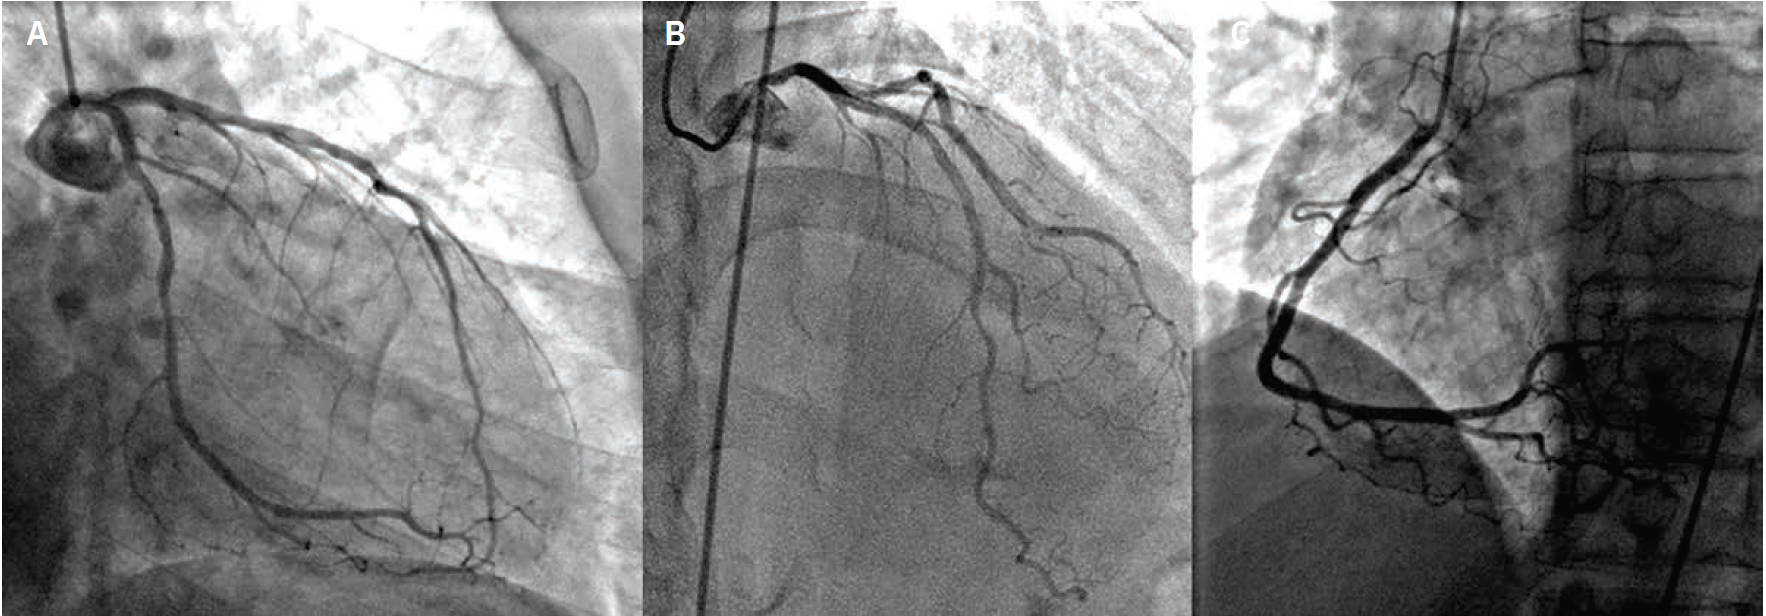

Imaging. Cardiac catheterization showed mild pulmonary hypertension, oxygen step up in right ventricle (RV) with Qp:Qs 2.8:1, severe native CAD, patent LIMA to LAD and RIMA to OM3. There was severe diffuse disease (90-95%) in the native LAD after the LIMA anastomosis (Figure 2, Video 2 [at end of case section]), which was the culprit behind the recent MI. Transesophageal echocardiogram (TEE) confirmed a large, antero-apical aneurysm and postinfarct VSD that measured up to 14 mm (Video 1 [at end of case section]). During multidisciplinary heart team discussion, he was deemed high risk for redo open heart surgery (LV aneurysmectomy and patch VSD closure) and was referred for percutaneous VSD closure.

Diagnostic cardiac catheterization with native coronary angiography as well as bypass graft angiography revealing severe, diffuse disease in the LAD distal to LIMA anastomoses.

LAD = left anterior descending artery; LIMA = left internal mammary artery